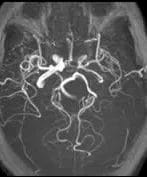

The left internal carotid artery (ICA) is of reduced calibre throughout its extra and intracranial course. In addition there is a marked focal narrowing with a flow gap at its origin. The axial fat saturated images through the petrous portion of the left ICA reveals high signal material surrounding the narrowed lumen. The appearances are suggestive of a partially recanalised dissection of the left ICA.